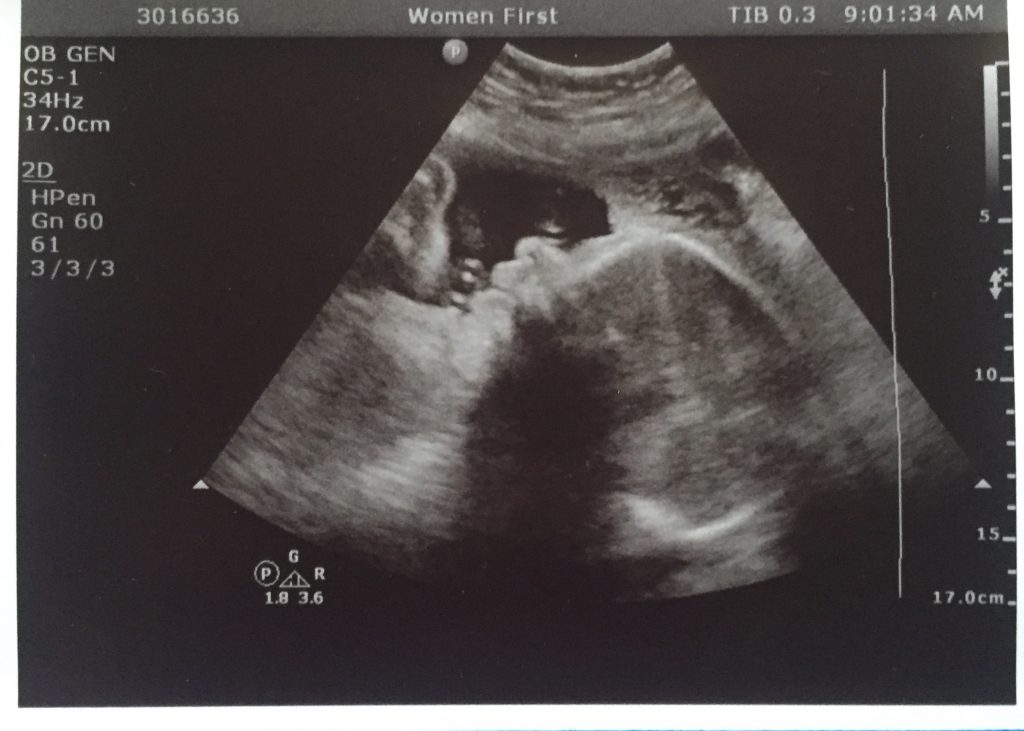

That appointment was yesterday–and even though when I was in with the ultrasound tech things seemed to be going well, the OBGYN did not interpret the numbers that way. Baby is now only growing in the 3rd percentile, which is not a great place to be. Numbers are compared not only against a global bell curve, but also against themselves over the course of the pregnancy. The numbers look almost okay on the normal bell curve, but look very troublesome compared to themselves. Things could still be fine, but it is definitely something that needs to be monitored closely. Baby is still gaining weekly, and measurements of the baby’s body parts look to be growing at a comparable rate to one another and the body as a whole. We had some weirdness in these numbers earlier in the pregnancy between legs/arms/torso that might have required genetic testing should that trend have continued.

In the actual ultrasound itself, the baby was sleeping, for once. Usually baby is moving around a ton and kicking hard, which has caused me to have to have extra ultrasounds a couple of times in order to get proper scans of the heart and other organs. Organs still looked good at this ultrasound, and all was much easier observed with a resting/sleeping babe for the first time. Baby is estimated to weight about 3 lb. 3 oz. right now and is expected to double in weight by birth. Mostly what babies are working on from 31 weeks on is gaining weight–most everything else is fully formed. They are adding fat and brain connections.